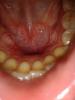

tia Опубликовано 28 июня, 2012 Поделиться Опубликовано 28 июня, 2012 (изменено) Подскажите, что это такое.Была у стоматолога. Сказал, что это воспаление десен. Сняли камень. Но воспаление не прошло. При этом оно появилось и на внутренней части десен. Как буд-то увеличилась костная ткань. Десна не болят, не кровоточат. Никакого беспокойства не вызывают. Единственное, ощущение, как от механического повреждения.Что это, что делать и как предотвратить появление в дальнейшем? Изменено 28 июня, 2012 пользователем tia Ссылка на комментарий

shishok Опубликовано 28 июня, 2012 Поделиться Опубликовано 28 июня, 2012 Это костные экзостозы(естественные образования в данном случае).Болеть могут,если чем-то травмированы(твёрдой пищей,наконечником от слюноотсоса).Всё пройдет само.Вы,главное,меньше обращайте на них внимания. Ссылка на комментарий